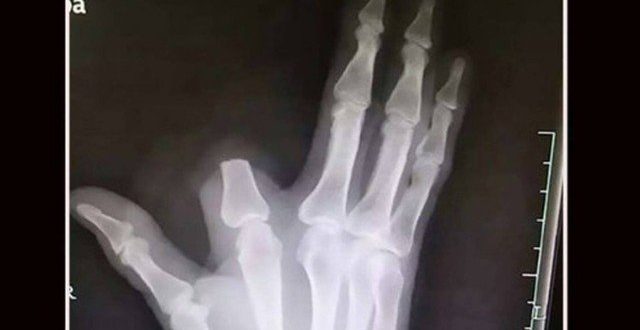

Parte de indicador decepada por agricultor

Parte de indicador decepada por agricultor Foto: Reprodução/Weibo

Um agricultor chinês, de 60 anos, tomou uma medida drástica após ser picado por uma cobra. Desesperado, Zhang decepou parte do dedo ferido a fim de evitar que o veneno se espalhasse.

Na verdade, o veneno da víbora que picara o agricultor é muito fraco, com efeito mínimo sobre humanos. Zhang cortou o pedaço do indicador à toa. E ele não pôde ser reimplantado.